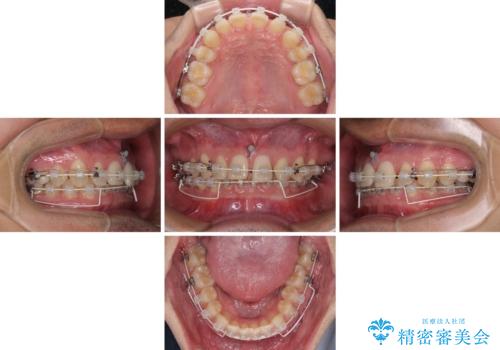

著しいディープバイトと隙間だらけの歯列

- 歯のデコボコと歯の隙間を気にして来院された患者様です。

隙間の原因は、埋伏や前後に重なってしまっている上顎小臼歯と、下の前歯が見えなくなるくらいのディープバイトで、それらを改善する必要がありました。

アンカースクリューを用いて下に位置している上顎前歯を持ち上げるとともに、ワイヤー装置によりディープバイトの原因である奥歯の傾斜を改善することで、矯正治療を行っていくこととしました。

また、矯正治療に際し、4本全ての親知らずと、埋もれている右上小臼歯を事前に抜去することとしました。